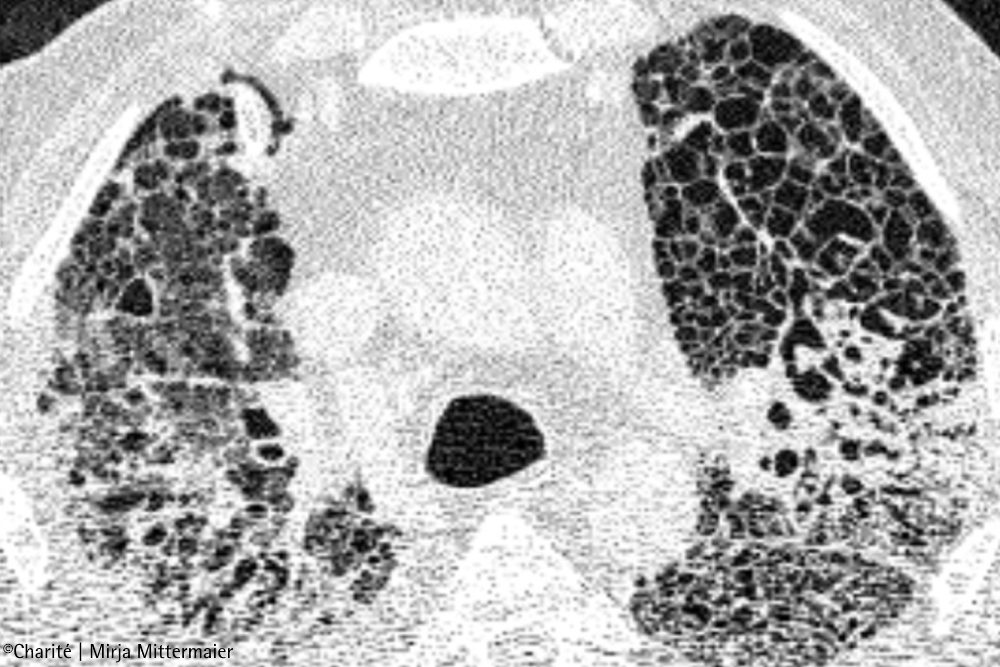

„Unsere Daten zeigen also eindeutig Parallelen zwischen COVID-19 und der chronischen Lungenfibrose auf“, resümiert Dr. Saliba. „Das erklärt vielleicht, warum einige Risikofaktoren für COVID-19 auch Risikofaktoren für die idiopathische Lungenfibrose sind – zum Beispiel Grunderkrankungen, Rauchen, ein männliches Geschlecht und ein Alter über 60 Jahre. Es gibt jedoch einen entscheidenden Unterschied zwischen den beiden Erkrankungen: Bei COVID-19 ist die Vernarbung zumindest potenziell reparabel.“ Das konnte das Forschungsteam anhand von CT-Bildern nachvollziehen. Bei COVID-19-Erkrankten, die mit der ECMO behandelt wurden, zeigten die Aufnahmen zunächst typische milchglasartige Trübungen, die sich im Verlauf der Erkrankung verdichteten und vernarbten. Bei Betroffenen, die von der ECMO-Behandlung entwöhnt werden konnten und genasen, gelang es dem Körper, die Verdichtungen allmählich aufzulösen – auch wenn in manchen Fällen deutliche Vernarbungsreste zurückblieben.